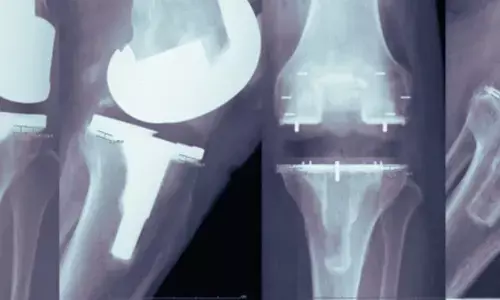

A key clinical advantage of PEEK highlighted in the review is its radiolucency. Unlike metal implants, PEEK does not create imaging artefacts on CT or MRI scans, allowing clearer visualisation of the bone–implant interface, and is light-weight. Coauthor Dr Abhishek Vaish explained, “The radiolucent nature of PEEK enables early detection of complications such as loosening or infection and improves postoperative monitoring.” He added that in procedures such as total knee arthroplasty, PEEK’s flexibility may promote more physiological load transfer and help preserve periprosthetic bone density.